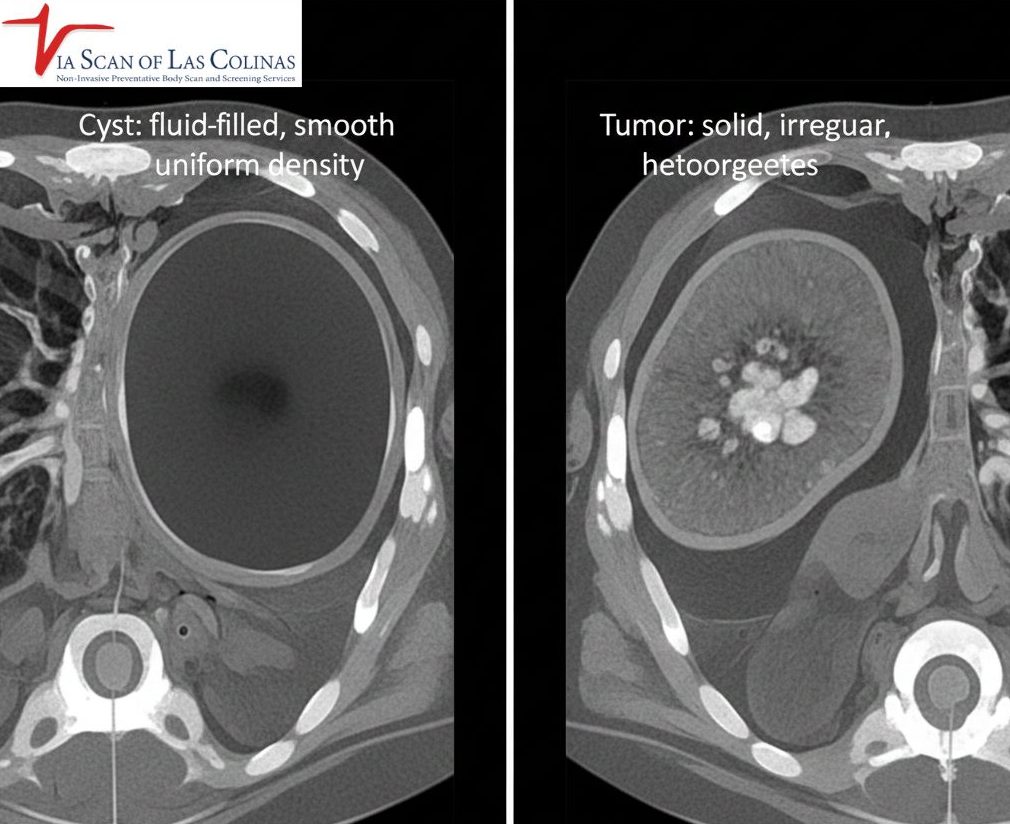

Difference between CYST and Tumor on CT scan

The very distinction between cyst and tumor on CT images is reduced to the contents of the mass. A cyst is a fluid-filled bubble – imagine it is a small water balloon in your body. In case of a CT, cysts are observed to be round and dark since they are filled with liquid, and not solid tissue. Tumours, on the other hand, are hard masses composed of real tissue or cells. Tumors do not appear the same on CT scans- they are usually brighter or more varied in appearance since solid tissue appears denser.

Simple cysts appear very characteristic on a CT scan and enable radiologists to identify them fast and be sure about them. Cysts are smooth, oval or rounded, and well delimited between the edges of the cysts; they are clean and neat looking and not irregular and jagged. Since they contain fluid, Cysts usually appear uniform in density on CT imaging, similar to fluid. Another characteristic that distinguishes them is that they do not enhance when contrast material is injected during scanning. Simple cysts have thin walls, including ultrasound-thin walls, so that they are barely visible, and the contents are homogenous, free of solid elements. All these typical characteristics inform radiologists that they are dealing with a benign and non-spreadable cyst that does not often need treatment or intervention.

Tumors appear very dissimilar to simple cysts in CT scans and the dissimilarity helps the radiologists assess the type of mass they are viewing. The solid tumors are brighter or more heterogeneous when compared to the dark and uniform cysts filled with fluid. In the issue of cyst vs tumor identification, radiologists seek masses that are irregular in shape, lack smooth edges or finger-like projections protruding into the surrounding tissues- things that cysts do not possess. Lots of tumours improve tremendously when contrast material is injected that is, they become bright on the scan as the solid tissue will absorb the contrast. Some mixed masses are not entirely solid or liquid and need close consideration. The ViaScan CT scan professionals in Irving, TX, offer the detailed scan that is required in the characterization and assessment of masses.